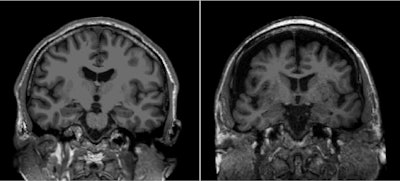

General age-related loss of brain matter aggravated by social isolation on T1-weighted cranial MRI of a 50-year-old (left) and 85-year-old (right).The authors noted that, at six-year follow-up, patients reporting social isolation via the Lubben scale had smaller hippocampus volumes and reduced cortical thickness on MR imaging. They also found that the higher the level of social isolation participants reported, the poorer their cognitive functions such as memory, processing speed, and executive capability.